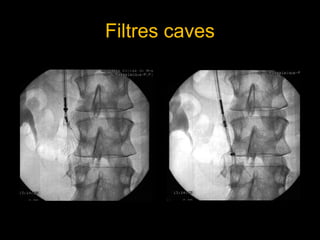

Interruption de la veine cave inférieure :

• Cette thérapeutique consiste à mettre en place par voie

percutanée un filtre dans la Veine Cave Inférieure afin d’éviter

les récidives d’EP à partir d’une TVP des membres inférieurs

• Cette thérapeutique à des indications rares. Elle se discute en

EP associée une TVP des membres inférieurs dans les

situations suivantes :

• Récidive d’EP malgré un traitement anticoagulant bien conduit

(hypocoagulabilité efficace)

• Après ombolectomie chirurgicale.

Filtres caves